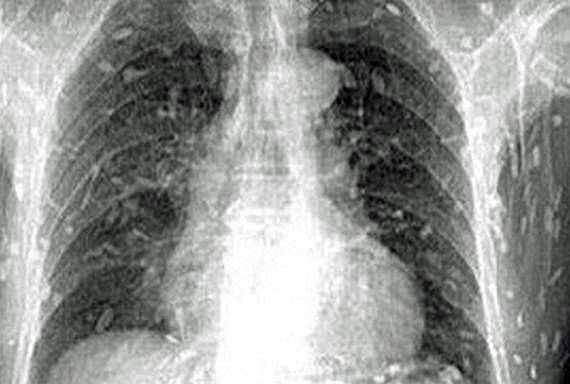

▼这张X光片中的景象可说是让人看的头皮直发麻!据称,这是一名中国男子在吃了生鱼片后全身发痒,到医院求诊后所拍下的,全身上下到处都是「白点」,成群条虫游走全身,光是想像就让人头皮发麻。

▼男子在就医后被转往广州市第八人民医院,医生认为他应是吃了受到污染的生鱼片才会被条虫寄生。条虫只存在淡水鱼类中,生鱼片中非常常见的「鲑鱼」便是其中一种。